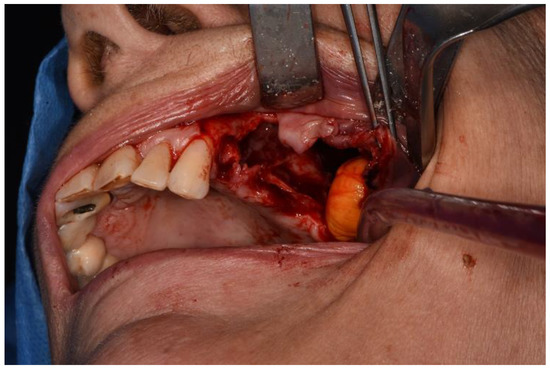

Figure 7. Buccal fat paddle isolation.

Surgeries 02 00040 g007

Figure 8. Buccal fat pad advancement.